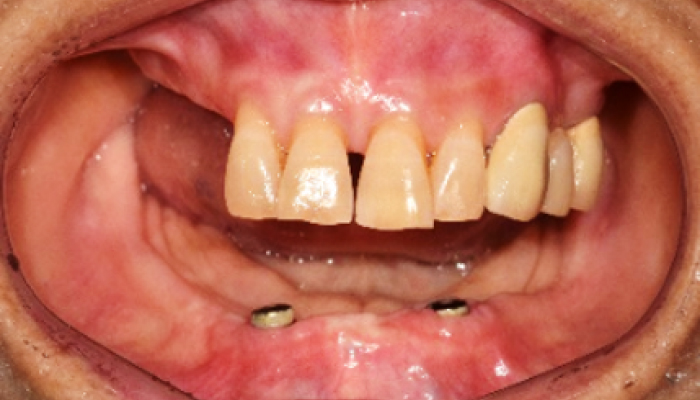

틀니 임플란트 전후 사례

• 식립전

식립후